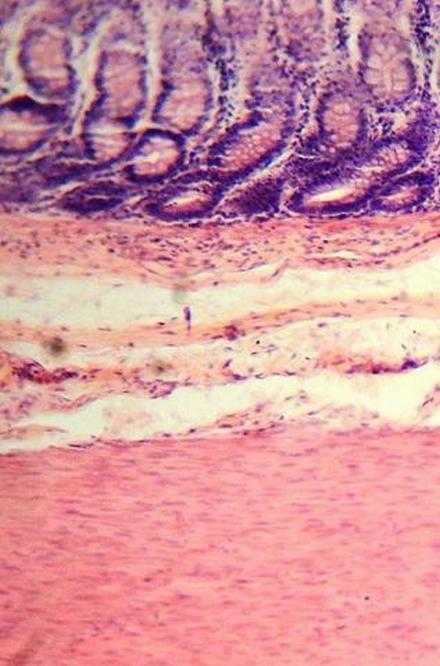

Crohn's Disease is an inflammatory disorder of the digestive tract. The inflammation can be very painful for an individual living with Crohn's Disease. It can cause him or her to experience diarrhea, bloating, fatigue, vomiting, and weight loss. Individuals living with Crohn's Disease are also at a greater risk of suffering colorectal cancer than others. The condition can lead to premature death for its sufferer.

(image courtesy of Juan Carlos Fonseca Mata)